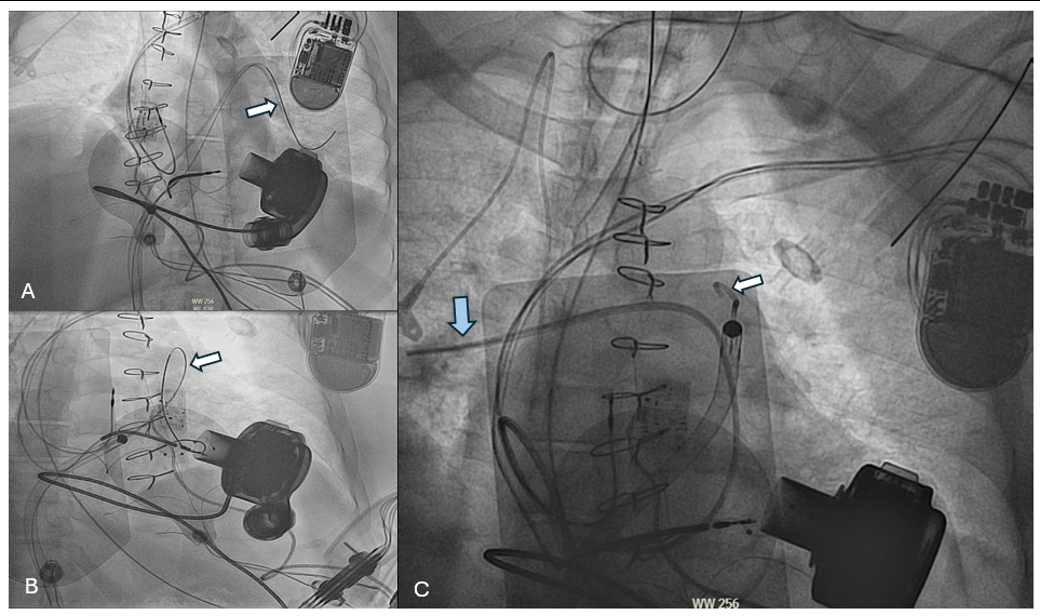

However, delivering the Impella RP across the tricuspid valve was challenging, as the guidewire became entangled under the ICD lead in a dilated RV. The previously placed guidewire was repositioned up, over, and away from the ICD lead (Figure 3A). We utilized the buddy-catheter technique, akin to the buddy-wire technique, to facilitate passage of Impella RP across the pulmonic valve with the assistance of the previously placed PA catheter (Figure 3A). The Impella RP was then successfully placed, and the PA catheter was left in place for hemodynamic monitoring (Figure 3B,C). Post-impella implantation improved the hemodynamics to a PAPi of 1.2, MAP of 70 mmHg, and a reduction in vasopressor requirements. The patient was ultimately transferred to a heart transplant center for further management.

Utilizing the “buddy-wire” technique for placement of an Impella RP is a viable method in patients with complex right-heart anatomy who may present with concurrent cardiogenic shock. The need to deliver the Impella RP across the tricuspid valve posed a risk of dislodging the RV CRT-D lead. Nonetheless, implementing the “buddy-wire” technique ensured the easier passage of the Impella, bypassing anatomical tortuosity.